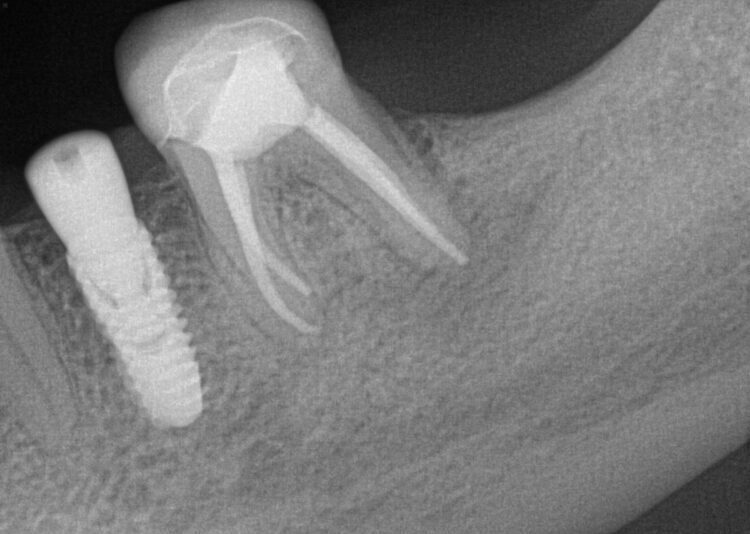

Hi, this implant was placed in June 2024. I have 3PAs (one from day of placement, one month later, and 9 month later). The intraoral picture of the soft tissue is from yesterday and tissue looks great… patient has no discomfort/pain either. She did have some discomfort between 2-3rd week after placement but subsided after taking antibiotics. On the one month xray, I may have missed the radioluency starting in apical 1/3.

Yesterday, I tapped the HA with the end of my mirror and wiggled the implant with no pain nor any perceptible movement. I am very suspicious, of course, about the radiolucency surrounding the apical 1/2 of the implant and am almost certain that the implant has failed (right?). I have removed failed implants at about 4 weeks (came out easily since still has not osseointegrated) but not at 9 months out…

Do you foresee this one coming out easily with reverse torquing? Also why does she not have any pain? What is the indication(s) for grafting a failed implant site… I’ve spoken to some who graft and others who don’t.